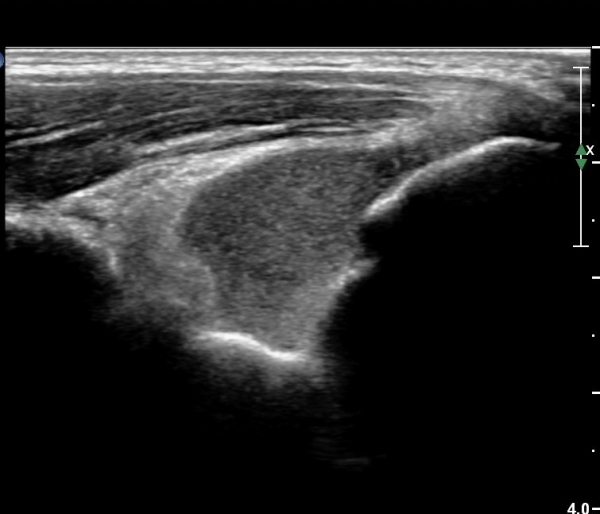

¿Ü»ó°ú¿Í ½ÅÀü°Ç Á¾´Ü¸é°Ë»ç¿¡¼­ ƯÀÌ ¼Ò°ß º¸ÀÌÁö ¾ÊÀ½(»çÁø 1)

³»»ó°ú¿Í ±¼°î°Ç Á¾´Ü¸é°Ë»ç¿¡¼­ ƯÀÌ ¼Ò°ß º¸ÀÌÁö ¾ÊÀ½(»çÁø2).

¼ÒµÎ Á¾´Ü¸é°Ë»ç¿¡¼­ ¼ÒµÎ¿Í ¿ä°ñµÎ Àü¹æ¿¡ ¼ö¾×Àú·ù°¡ °üÂûµÊ(»çÁø 3, 4).

ÁÖµÎ¿Í Á¾´Ü¸é°Ë»ç¿Í Ⱦ´Ü¸é°Ë»ç¿¡¼­ ÁֵοͿ¡ ÀÌÁúÀû¿¡ÄÚ¸¦ º¸ÀÌ´Â

´Ù·®ÀÇ ¼ö¾×Àú·ù°¡ °üÂûµÊ(»çÁø 5, 6).